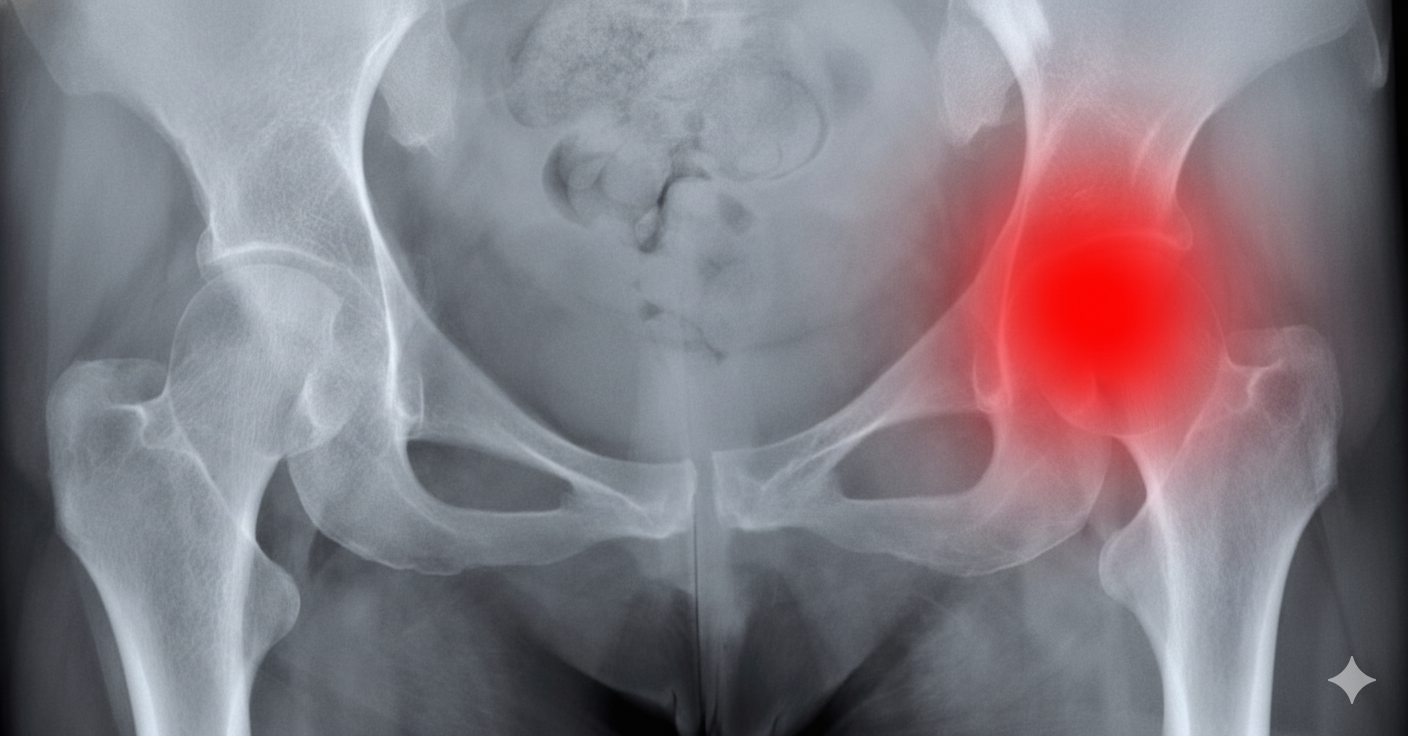

Tumores Pélvicos: Desafios e Evoluções na Abordagem Cirúrgica Multidisciplinar

Os tumores localizados na região pélvica formam um grupo bastante diversificado de neoplasias que comprometem órgãos como o útero, ovários, bexiga e reto. Devido à

Esses tipos de tumores são prevalentes em nosso meio e devem ser avaliados de maneira individualizada. Segundo o INCA, o tumor de cólon e reto é o terceiro mais comum em homens e o segundo em mulheres (excluindo-se tumores de pele), seguidos dos tumores de estômago, esôfago, corpo do útero e ovário. Para cada situação, será necessário atenção especial individualizada.